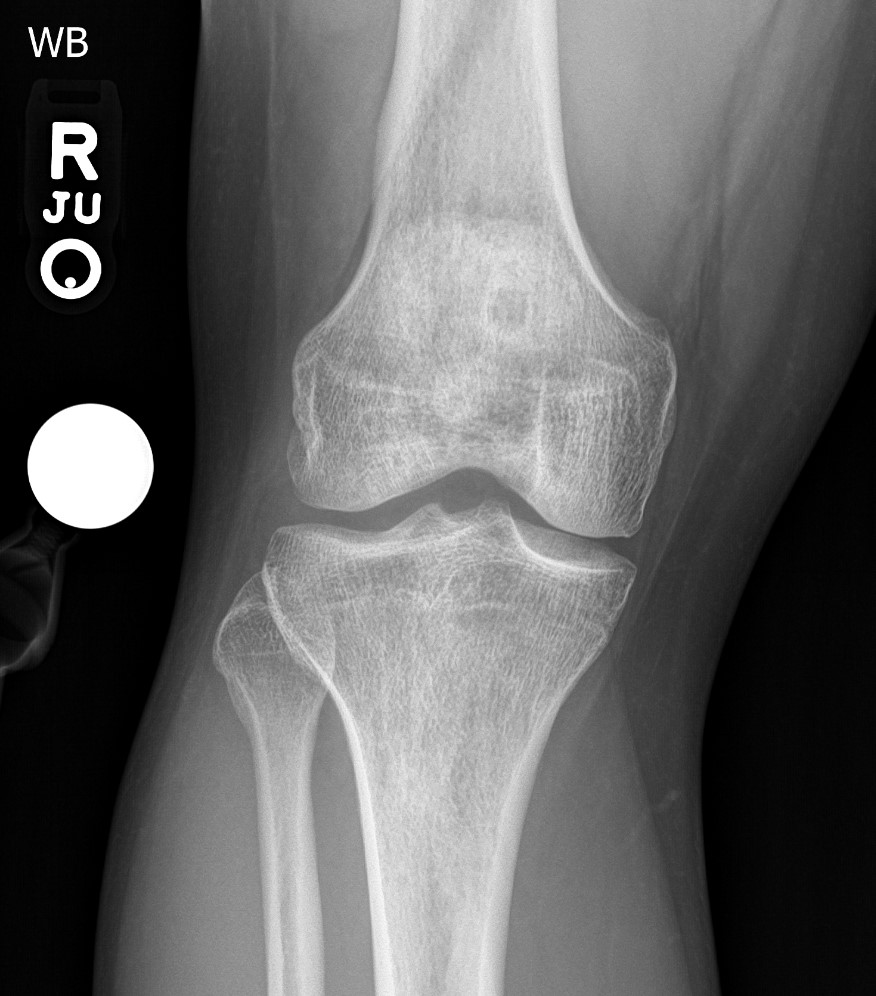

gout arthritis ( rid3567 )

by andrew kingzett taylor, md ( 3.5 )